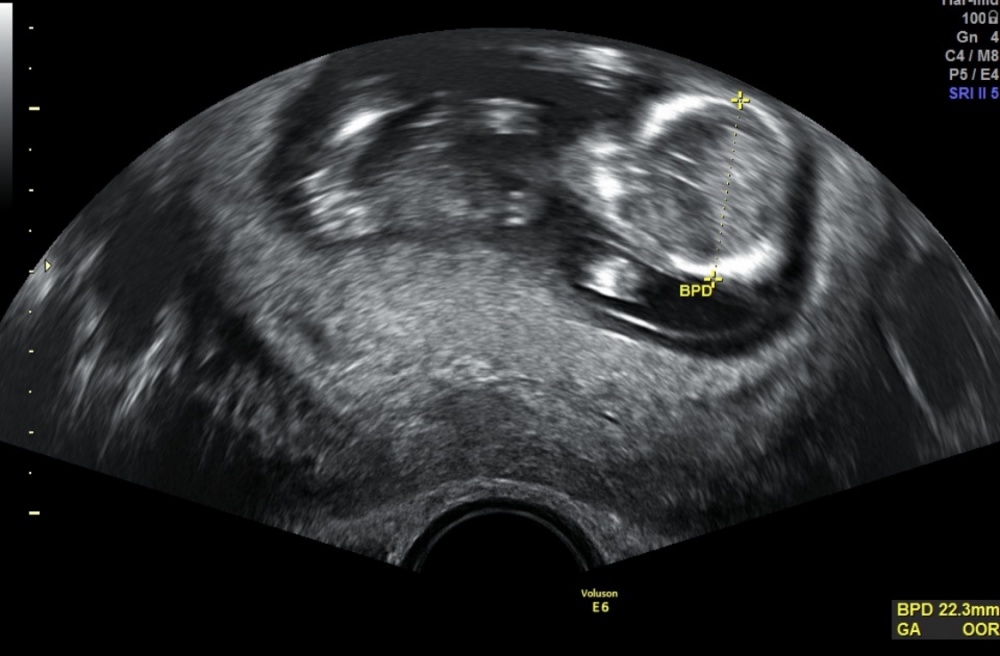

Ich versuch noch einmal mein Glück, habe heute ein neues US-Bild bekommen 😁

Hoffe ihr könnt dieses mal bissl was erahnen bzw eine Tendenz abgeben 😪

@Michi1712 laut Nub Theorie, würde ich auf einen Jungen tippen.